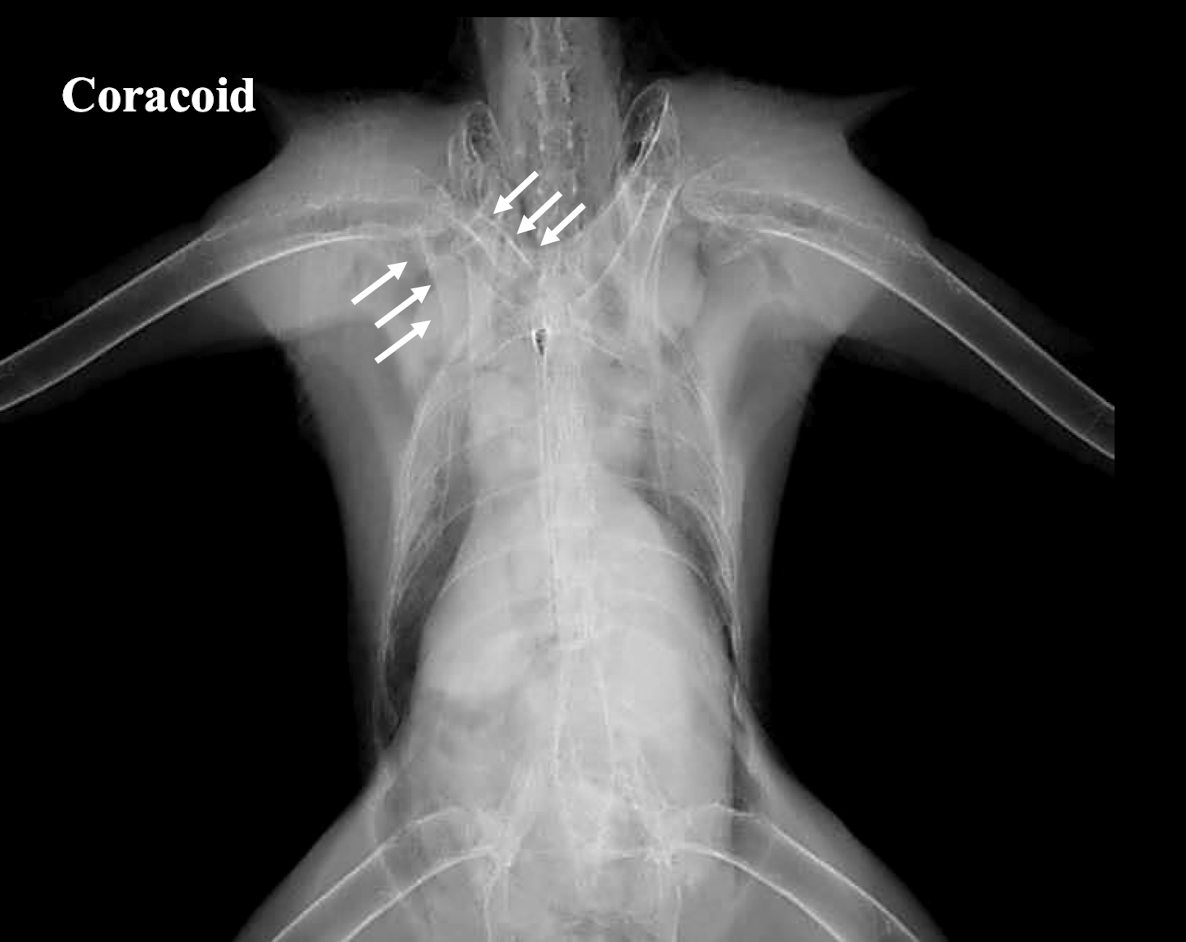

Coracoid fracture

Name two common skeletal lesions identifiable on avian radiographs.

Fracture and Luxation.